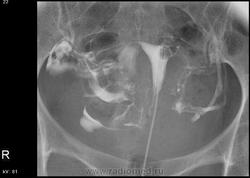

С учетом представленных нескольких снимков по интервалу времени, а следовало делать отсроченный, складывается впечатления о дефекте наполнения контрастного вещества дна матки, да и левая труба четко не законтрасирвона и контраста нет свободно распределяющегося в брюшной полости, из этого следует делать вывод по Вашим снимкам либо это следствие наличие пузырьков воздуха(а перед исследованием врач-гинеколог выпускет свободный воздух в шприце с контрастным веществом), либо это следствие образования матки или яичника и минимум после Вашего исследования надо проводить УЗИ-малого таза.

В заключении написала, что левая труба непроходима. Дефект наполнения посчитала за воздух, такую картину вижу уже не в первый раз. УЗИ сделано несколько раз перед исследованием (в разные дни цикла), без патологии.

Исследование проведено с нарушениями: воздуху в полости матки абсолютно нечего делать, эта воздушная пробка могла стать причиной отсутствия контрастирования левой трубы, так что диагностическое значение исследования снижено. Экстравазация тазовых вен ни о чем плохом не говорит. Картина распределения контаста в правой половине малого таза - тоже без патологии.

Интравазация околоматочных сосудов. Подобные наблюдения демонстрировались на сайте. Надеюсь всё прошло без санитарных потерь?